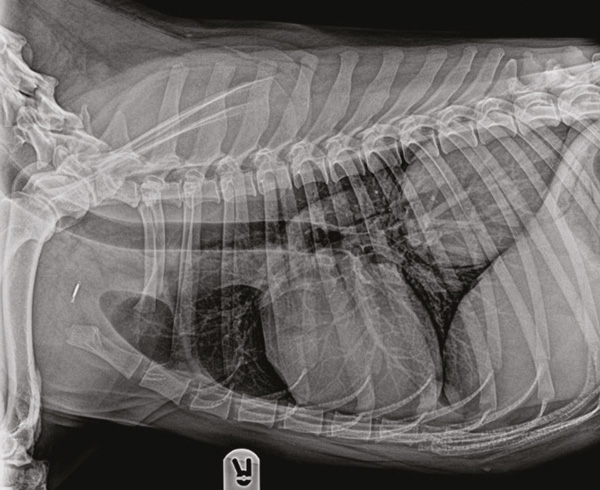

Figure 1: Right lateral view of the thorax. A large mass can be noted in the right caudal lung lobe.

Radiographs highlighted a lung mass, along with a polyostotic, ‘palisading’ periosteal proliferation in all four distal limbs.

CT of the thorax and abdomen revealed a large (8.4 x 8.1 x 6.4 cm) pulmonary mass located in the right caudal lung lobe. No metastases were detected.